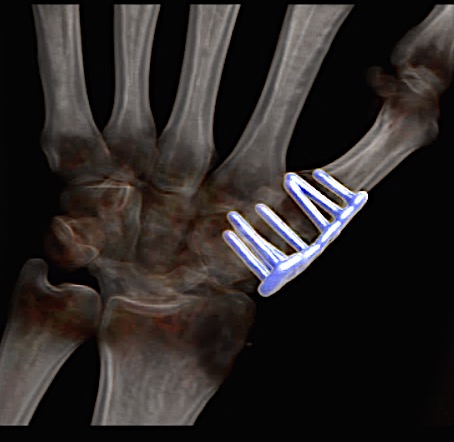

Case 1:

A 64-year-old male suffered a multi-fragmentary fracture of his right thumb metacarpal (Fig 1). An adapted 12-hole strut plate from the variable angle locking hand system was the implant of choice for fixation (Figs 2 - 4).

The strut plate provided good stability in a comminuted extraaricular fracture pattern and enables immediate mobilization. Bone callus formation was not witnessed during the healing process.